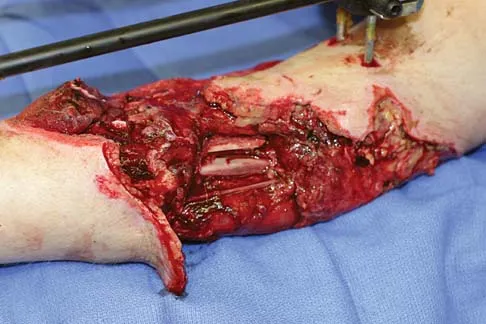

Question 55

A healthy 25-year-old man sustains a grade IIIB open tibial fracture. Following appropriate debridement, irrigation, and stabilization with an external fixator, the soft-tissue injury is shown in Figure 30. What is the most appropriate definitive soft-tissue coverage procedure?

Explanation